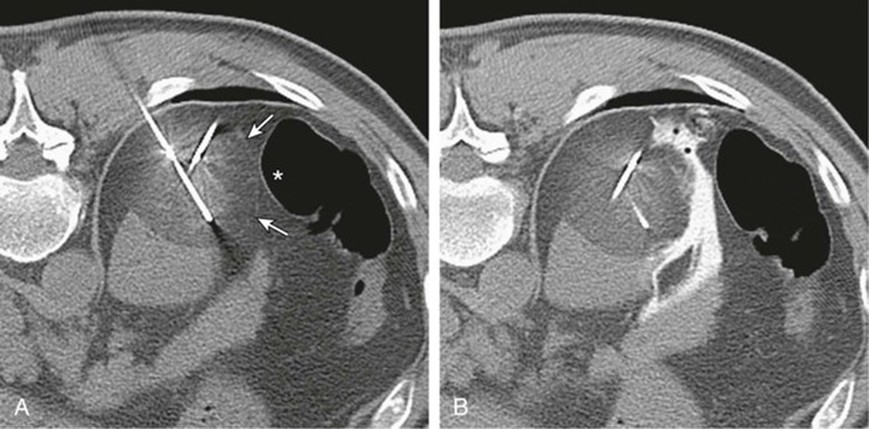

Cắt lớp vi tính

CT được sử dụng rộng rãi cả trong chẩn đoán và phân giai đoạn ung thư biểu mô tế bào thận. Trên CT không tiêm thuốc cản quang, tổn thương thường có tỷ trọng mô mềm, dao động trong khoảng 20–70 đơn vị Hounsfield. Các khối u lớn thường có những vùng hoại tử, và khoảng 30% trường hợp có vôi hóa. Trong thì vỏ–tủy, từ 25 đến 70 giây sau tiêm thuốc cản quang, ung thư biểu mô tế bào thận biểu hiện mức độ ngấm thuốc thay đổi, thường thấp hơn so với vỏ thận bình thường. Các tổn thương nhỏ có thể ngấm thuốc tương đương nhu mô vỏ thận và do đó khó phát hiện.

Nhìn chung, các khối u nhỏ thường ngấm thuốc đồng nhất, trong khi các khối u lớn hơn có hình ảnh ngấm thuốc không đều do sự hiện diện của các vùng hoại tử. Phân nhóm tế bào sáng có thể cho thấy mức độ ngấm thuốc mạnh hơn rõ rệt.

Thì vỏ–tủy cũng là thì tối ưu để đánh giá giải phẫu mạch máu, bao gồm xâm lấn tĩnh mạch thận và các biến thể động mạch, đặc biệt khi đang cân nhắc phẫu thuật cắt thận bán phần. Sự phát triển của khối u vào trong lòng hệ tĩnh mạch, đặc biệt là tĩnh mạch thận, xảy ra trong khoảng 10% trường hợp (dao động 4–15%). Tiên lượng ở những bệnh nhân có xâm lấn tĩnh mạch chủ dưới xấu hơn rõ rệt so với trường hợp chỉ xâm lấn tĩnh mạch thận, do đó việc nhận diện chính xác trên CT có ý nghĩa quan trọng.

Thì nhu mô thận, từ 80 đến 180 giây sau tiêm thuốc, là thì nhạy nhất để phát hiện các vùng ngấm thuốc bất thường.

Thì bài xuất ít giá trị hơn, nhưng vẫn quan trọng trong việc đánh giá giải phẫu hệ thống đài bể thận, đặc biệt ở những bệnh nhân có khả năng là ứng viên cho phẫu thuật cắt thận bán phần.